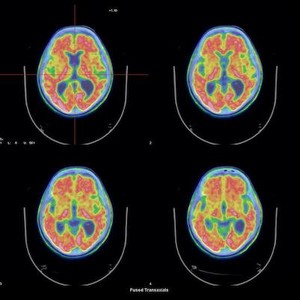

Secondo e ultimo incontro con il ciclo Argomenti di medicina nucleare: diagnostica funzionale e terapia, a cura di Angelo Corso, direttore della medicina nucleare dell’Ospedale Sant’Anna, per l’Università popolare Como – Auser.

L’appuntamento propone la descrizione della capacità della medicina nucleare di analizzare la funzione dei principali organi e apparati e valutarla quantitativamente, e, quindi, definire con accuratezza anche la risposta alle terapie. Tutto questo a differenza della diagnostica radiologica, pressoché esclusivamente basata sulla morfologica, dove, invece, la medicina nucleare è tuttavia meno performante.

Le due branche della diagnostica quindi si compendiano vicendevolmente. In particolare oggi si parlerà della Pet – Tac nell’Alzheimer. L’ausilio diagnostico della vera intelligenza artificiale (la sigla pet sta per “Tomografia a emissione di positroni”, ndr) riguardo alla più frequente malattia neuro degenerativa: lo stato dell’arte.